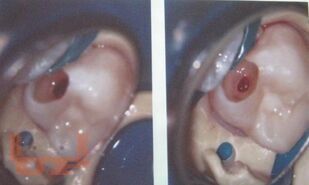

В учебно-методическом пособии рассматриваются основные принципы и методы эндодонтического лечения пульпитов и периодонтитов в детской стоматологической практике. Материал базируется на имеющихся в отечественной и зарубежной литературе современных представлениях по данной проблеме. Издание рекомендуется для использования в основных образовательных профессиональных программах слушателей системы последипломного образования и практической деятельности врачей-стоматологов, клинических ординаторов, аспирантов.